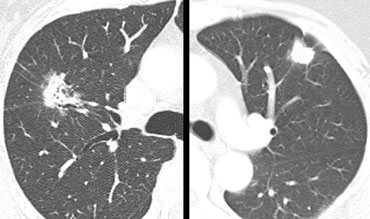

Corona radiata sign in a malignant lesion with spiculation at the margin. Corona radiata sign in a malignant lesion with spiculation at the margin.

Margin

• Corona radiata sign - highly associated with malignancy (figure)

• Lobulated or scalloped margins - intermediate probability

• Smooth margins - more likely benign unless metastatic in origin

On the left two solitary pulmonary nodules.

Based upon the morphology, which lesion has the most malignant features?

The lesion on the far left has a spicuated margin and has lucencies within it.

The lesion next to it is lobulated in contour and has some spicules radiating to the pleura.

It is however homogeneous in attenuation.

Based on these findings we should be most concerned that the lesion on the far left is malignant.

It proved to be an adenocarninoma, while the other one was a fungal infection.

The lucencies and frank air bronchograms should not mislead you in thinking that it probably is infection.